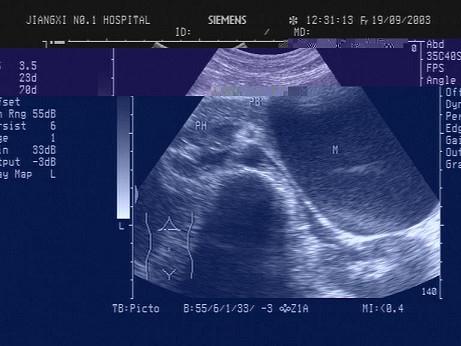

问题 患者,急性胰腺炎治疗后,超声见胰腺尾前方7cm大小的囊性光团,如图所示,考虑为?(?)

选项 A.胰腺假性囊肿 B.胰腺炎 C.胰腺肿瘤 D.胰腺脓肿 E.胰腺真性囊肿

答案 A